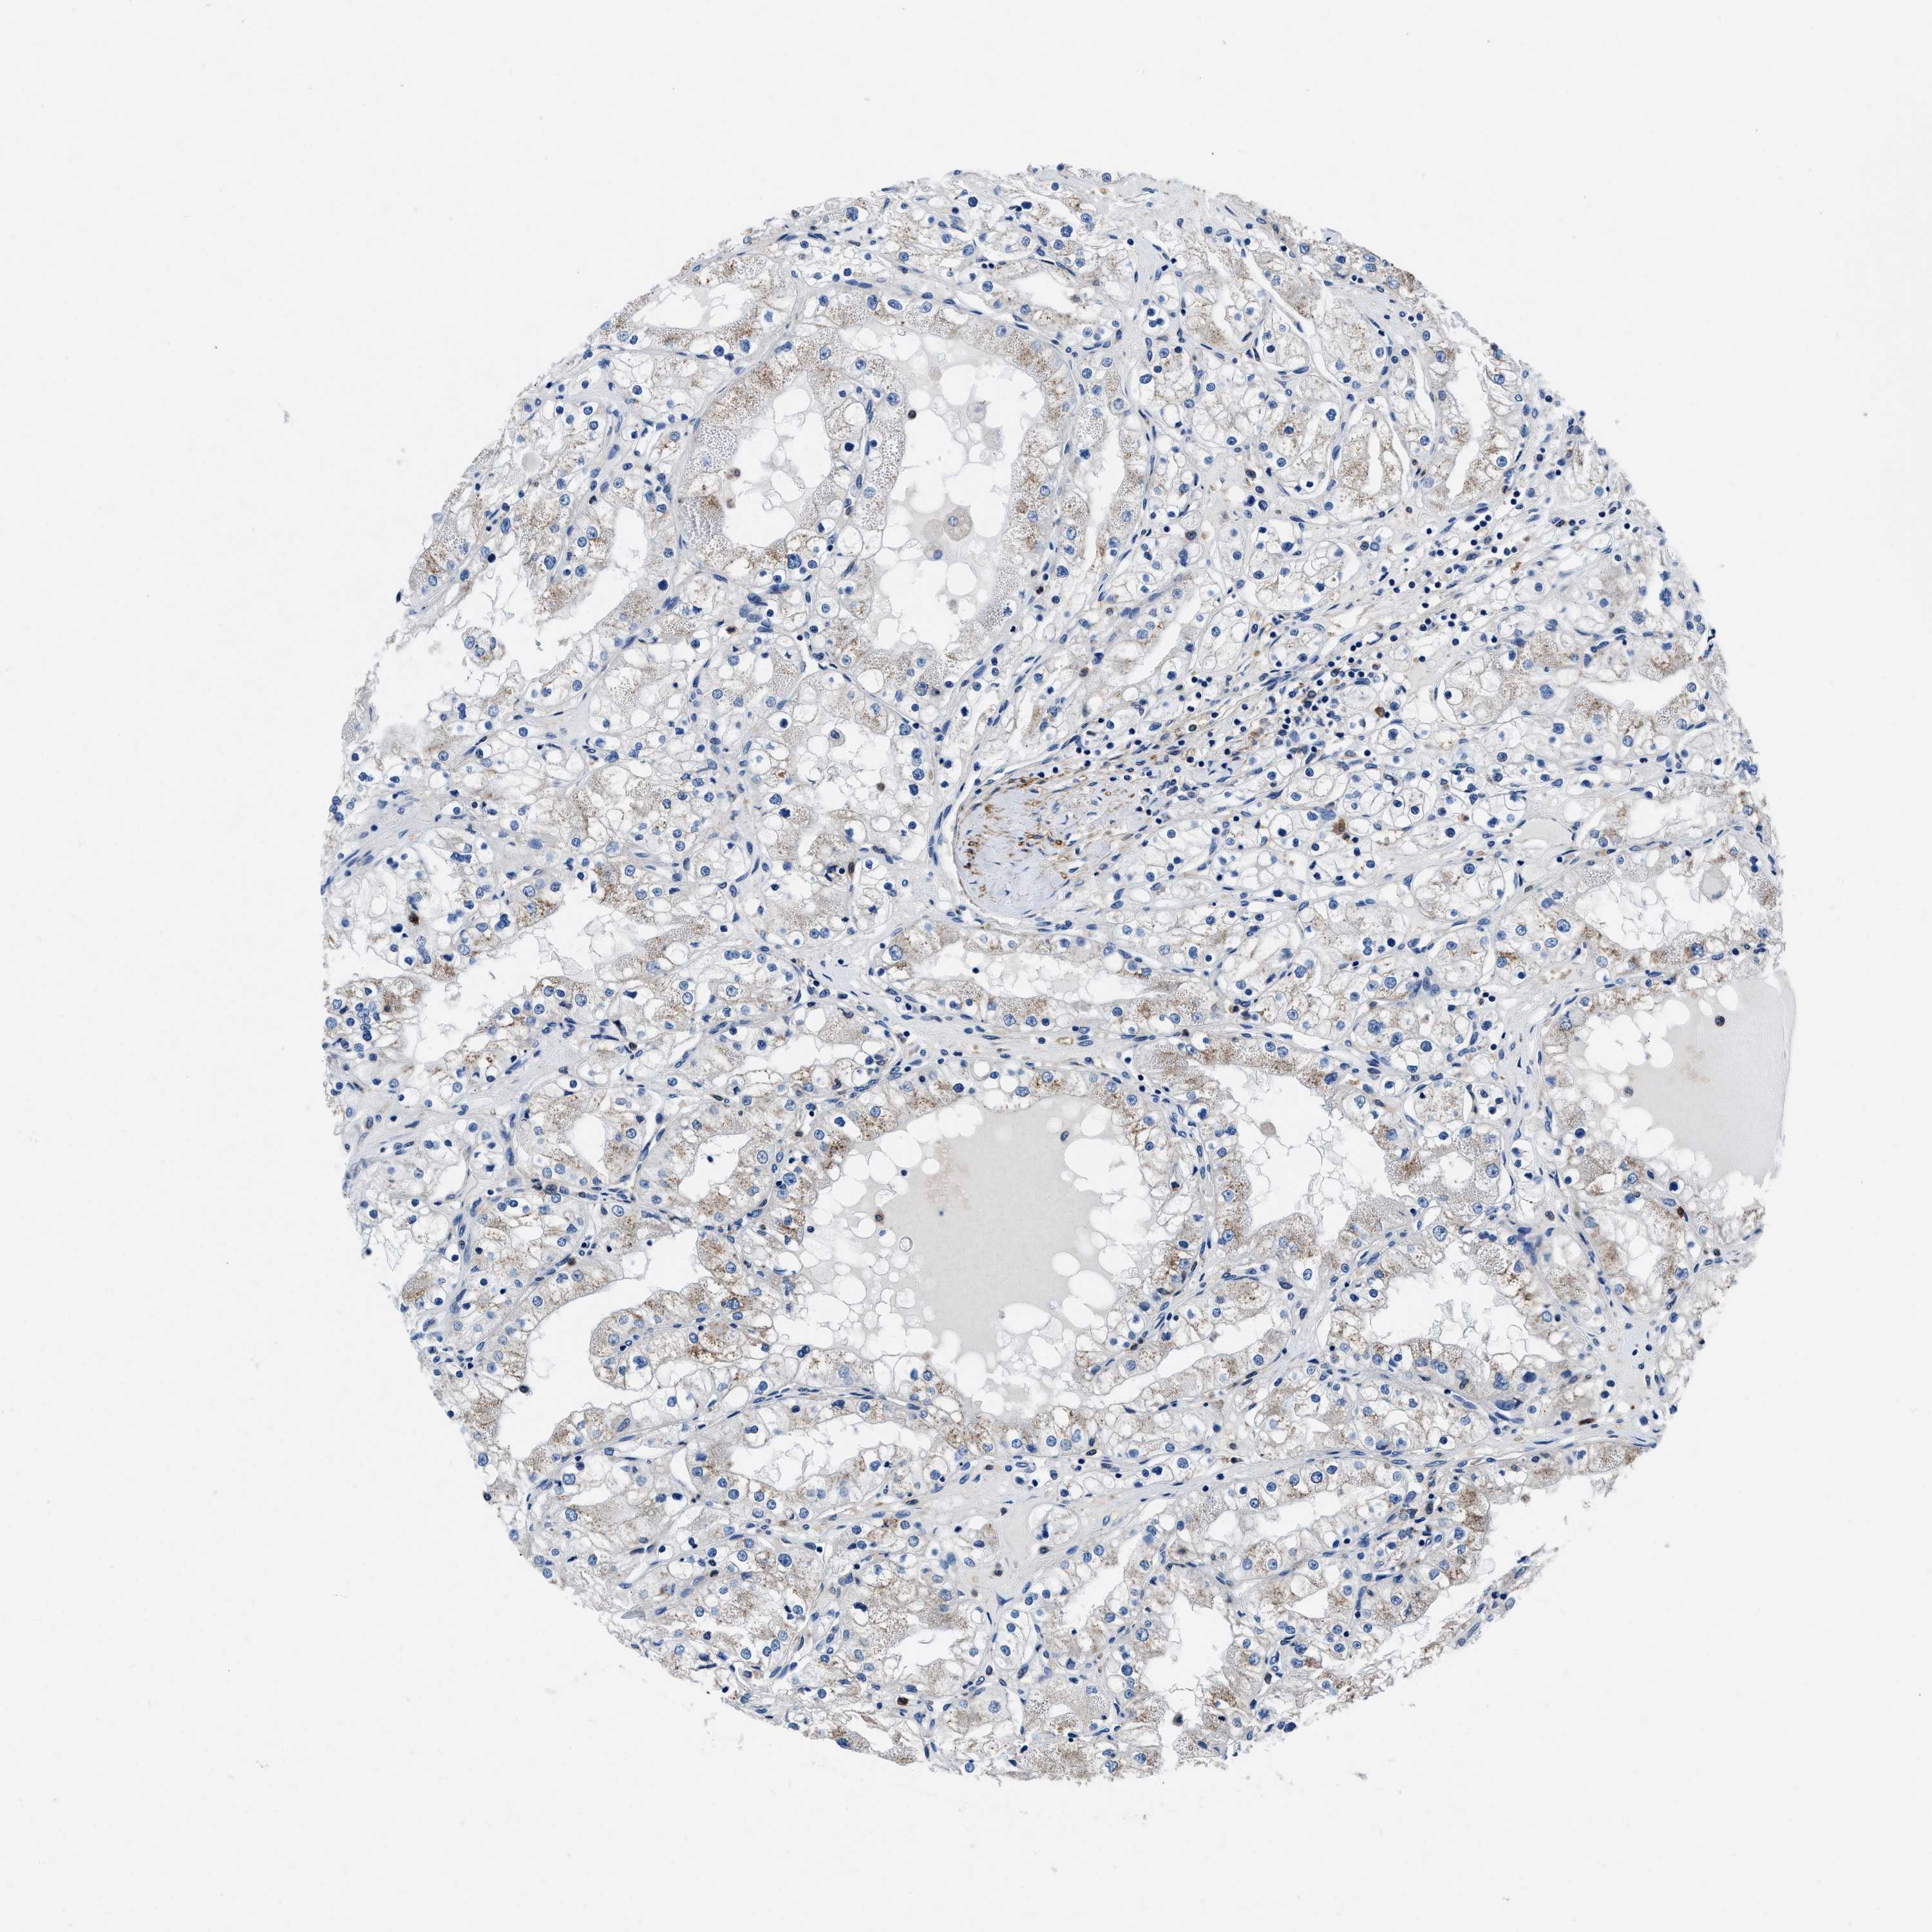

KIDNEY RENAL CLEAR CELL CARCINOMA (VALIDATION) - Interactive survival scatter ploti

The Survival Scatter plot shows the clinical status (i.e. dead or alive) for all individuals in the patient cohort, based on the same data that underlies the corresponding Kaplan-Meier plots. Patients that are alive at last time for follow-up are shown in blue and patients who have died during the study are shown in red.

The x-axis shows the expression levels (FPKM) of the investigated gene in the tumor tissue at the time of diagnosis. The y-axis shows the follow-up time after diagnosis (years). Both axes are complimented with kernel density curves demonstrating the data density over the axes. The top density plot shows the expression levels (FPKM) distribution among dead (red) and alive patients (blue). The right density plot shows the data density of the survived years of dead patients with high and low expression levels respectively, stratified using the cutoff indicated by the vertical dashed line through the Survival Scatter plot. This cutoff is automatically defined based on the FPKM cutoff that minimizes the p-score. The cutoff can be changed by dragging the vertical line or by entering a cutoff value in the square labeled "Current cut-off".

Under the Survival Scatter plot the p-score landscape (black curve; left axis) is shown together with dead median separation (red curve; right axis). Dead median separation is the difference in median mRNA expression between patients who have died with high and low expression, respectively. It is calculated as follows: median FPKM expression of dead patients with high expression - median FPKM expression of dead patients with low expression. This is intended to aid the user in visually exploring custom cutoffs and the associated p-scores and dead median separation.

Individual patient data is displayed and can be filtered by clicking on one or more of the category buttons on the top of the page. Categories describing expression level and patient information include: high, low, alive, dead, female, male and tumor stages. The scale of the x-axis can be toggled between linear and log-scale by clicking on the "x log" button. Mouse-over function shows TCGA ID, patient information and mRNA expression (FPKM) for each patient.

& Survival analysisi

Kaplan-Meier plots summarize results from analysis of correlation between mRNA expression level and patient survival. Patients were divided based on level of expression into one of the two groups "low" (under cut off) or "high" (over cut off). X-axis shows time for survival (years) and y-axis shows the probability of survival, where 1.0 corresponds to 100 percent.

NEU1 is not prognostic in Kidney Renal Clear Cell Carcinoma (validation)

Best expression cut offi

Based on the FPKM value of each gene, patients were classified into two groups and association between prognosis (survival) and gene expression (FPKM) was examined. The best expression cut-off refers the FPKM value that yields maximal difference with regard to survival between the two groups at the lowest log-rank P-value. Best expression cut-off was selected based on survival analysis .

When clicking on this number, the vertical dashed line indicating cut-off, the interactive survival plot, and the Kaplan-Meier curve will be adjusted to show results based on the best expression cut-off.

: 1.09

TCGA RNA samplesi

RNA-seq data is reported as average FPKM (number Fragments Per Kilobase of exon per Million reads), generated by the The Cancer Genome Atlas (TCGA) .

Normal distribution across the dataset is visualized with box plots, shown as median and 25th and 75th percentiles. Points are displayed as outliers if they are above or below 1.5 times the interquartile range. FPKM values of the individual samples are presented next to the box plot.

Average pTPM 1.4

Number of samples 100